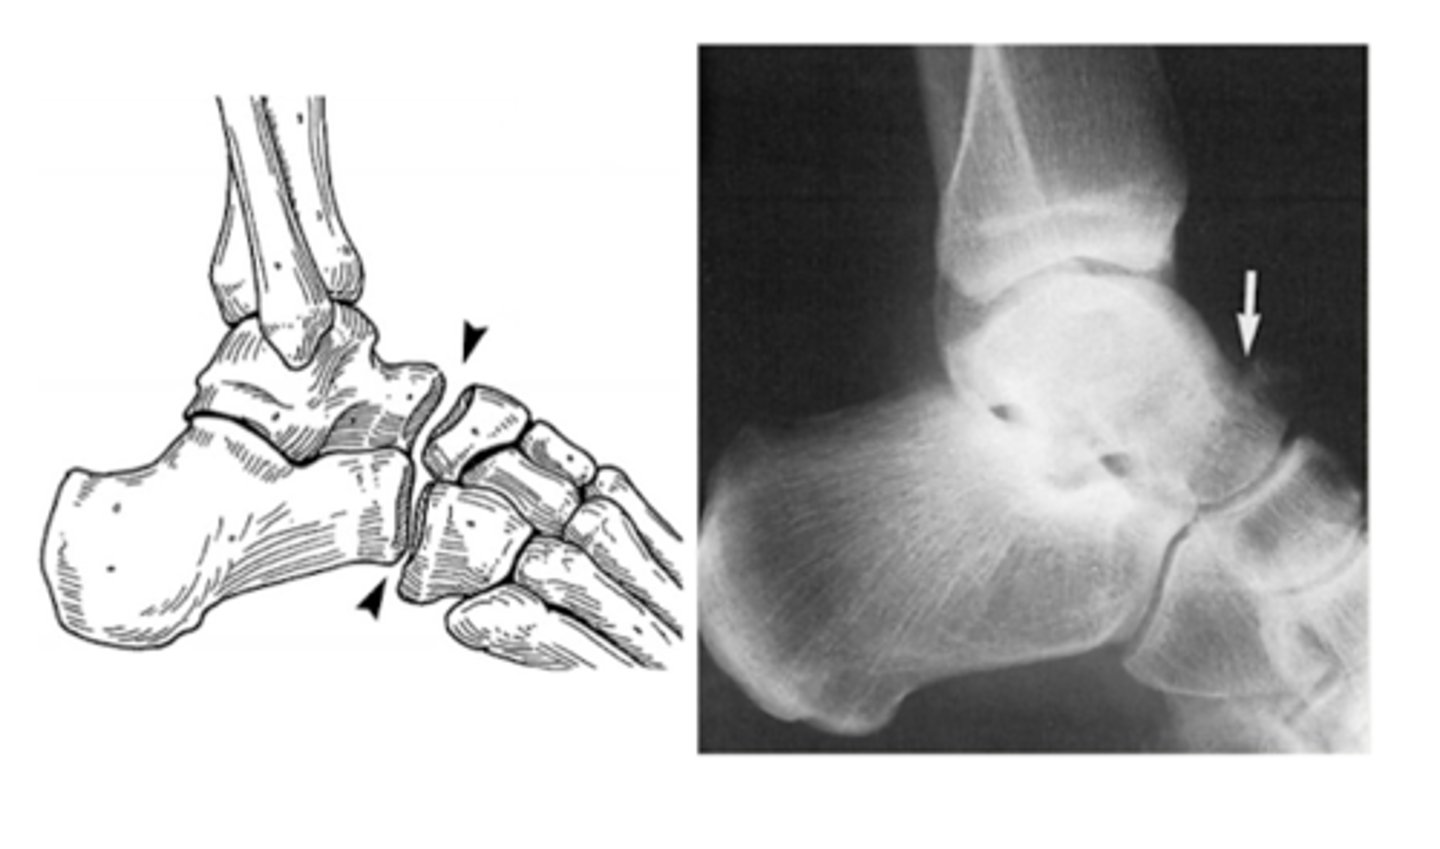

What joint is involved in a Lisfranc injury/fracture?

TMT (tarsometatarsal) joint

- between the articulation of the medial cuneiform and the base of the 2nd MT

What is the treatment for a Lisfranc injury/fracture that is <2mm?

casting for 6 weeks

- cannot bear weight